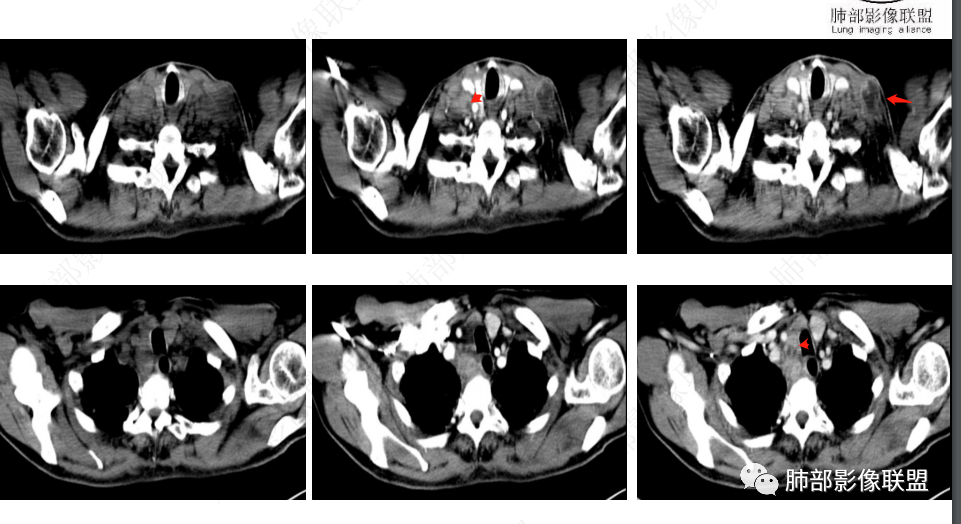

2、影像特点:双肺多发结节及条索影,边缘清晰,右肺上叶可见网格影,右侧胸腔少量积液;颈部、纵膈及腹部多发淋巴结肿大,大部淋巴结强化不均,呈环形强化,内部见低密度坏死区,部分淋巴结坏死不明显,尤其是腹部淋巴结密度较均匀。